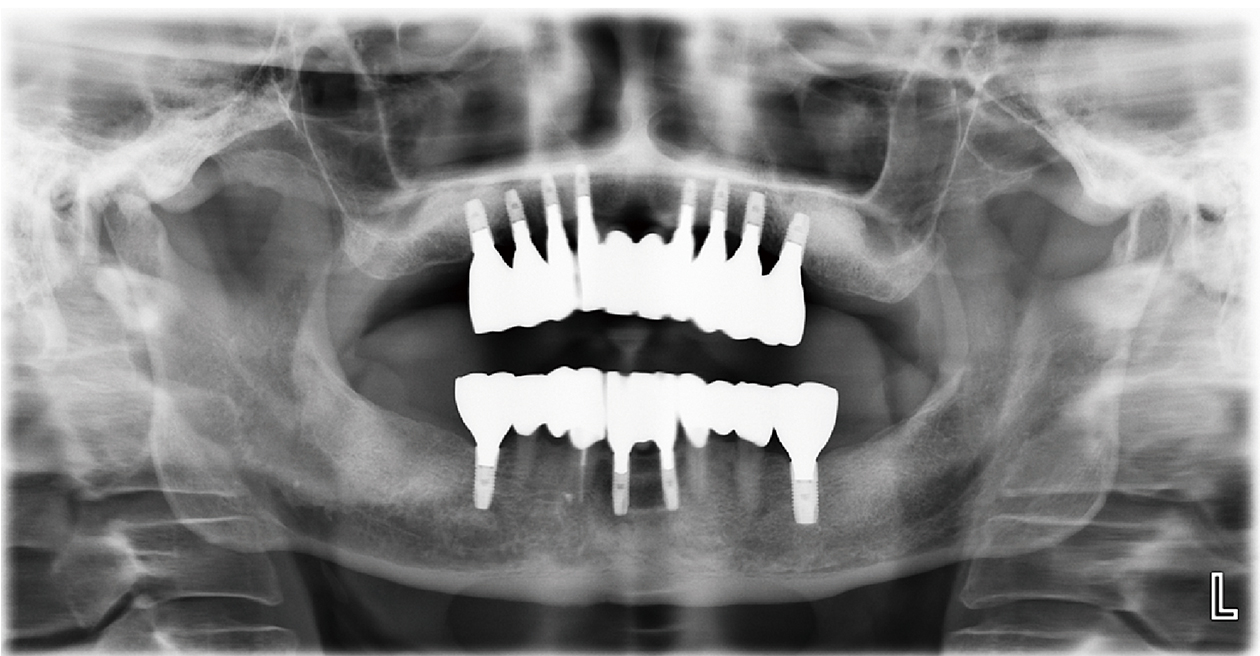

│3D 列印植牙靜態導板與動態導航在臨床上的應用

3D 列印技術在牙科的應用日益成熟,其中,電腦輔助靜態植牙手術導板(Computer-Assisted Surgical Guide)對於提升植牙手術的精準度與效率有極大幫助。透過數位口腔掃描與電腦斷層3D影像,醫師可以先在電腦上模擬植牙位置,並透過 3D 列印技術製作專屬於病人的植牙導板。此技術能確保植體位置、角度與深度的準確性,降低醫師在手術過程中的誤差,同時減少病人的手術創傷與恢復時間。此外,3D 列印植牙導板特別適用於多顆植牙或全口無牙的病人,能提升植體的長期穩定性與成功率。(圖一~圖五) 此外,除了靜態導版,動態植牙導航技術 (Navigation)的發展,更是植牙手術的一大躍進!

• 圖一

• 圖二

• 圖三

• 圖四

• 圖五

經由攝像頭紅外線感應,螢幕畫面的即時影像能顯示植牙位置,如同GPS定位系統,輔助牙醫師更精確置放植牙。